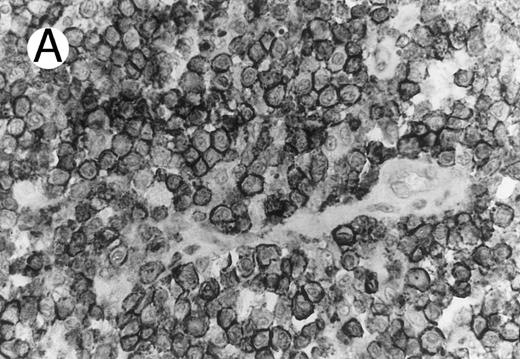

Cytotoxic granule antigen expression in a common form of ALCL (Table 2; case 11). (A) Immunostain for CD30 highlights sheets of large tumor cells. (B) The tumor cells of this case display granular cytoplasmic TIA-1 immunoreaction with paranuclear accumulation in the Golgi region. (C) Strong cytoplasmic perforin reaction is shown in the same case. (sABC-peroxidase technique, hematoxylin counterstain, original magnification × 400.)

Anaplastic large cell lymphomas of T-cell and ‘null’-cell type.The results are summarized in Tables 1 and 2. Twenty-three (70%) of the 33 ALCL cases revealed TIA-1 positivity in the lymphoma cells. In 20 of the 23 positive cases virtually all tumor cells were positive, while in the remaining 3 cases less than half of the tumor cells showed TIA-1 positivity. Sixteen TIA-1+ cases displayed a T-cell phenotype, six revealed a null-cell phenotype, and one had an ambiguous phenotype staining with both T-cell and NK-cell markers. Positive staining was seen in 13 out of 19 (68%) CS forms, and all (100%) of the 6 HR and 2 SCP variants. The typical staining pattern was granular and cytoplasmic, with frequent paranuclear staining in the Golgi region (Fig 1). The 2 SCP cases showed homogenous granular TIA-1 reaction in both the small cell and the CD30+ large cell components. In addition, 2 of the 3 AIDS-associated cases (67%) showed positive staining, whereas none of the 3 PC forms marked for TIA-1. Beside neoplastic cell staining, small reactive lymphocytes with a similar typical granular staining pattern were seen in all cases investigated. These lymphocytes represented scattered interfollicular and intrafollicular small cells, but in some cases accounted for up to 40% of the non-neoplastic paracortical lymphocytes either in the involved or uninvolved lymph node regions. Cytoplasmic TIA-1 staining also occurred in normal granulocytes, but with a less distinct granular pattern than in positive lymphocytes. In some cases, occasional epithelioid histiocytes displayed weak, diffuse cytoplasmic staining. TIA-1+ tumor cells revealed a distinct granular staining pattern that was always easily distinguishable from reactions of granulocytes and epithelioid histiocytes.